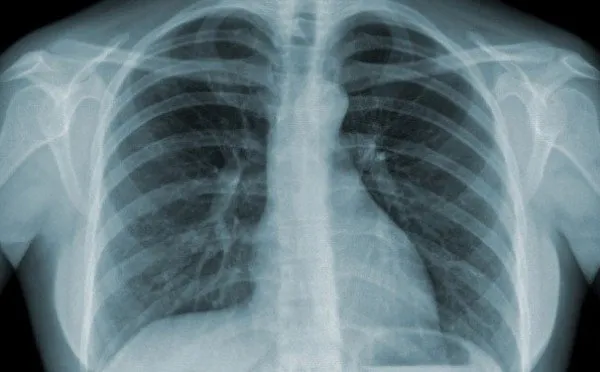

• X-quang ngực: Phim chụp X-quang có thể cho thấy hình ảnh tổn thương phế nang lan tỏa ở cả hai bên phổi, có xu hướng tiến triển nặng dần.